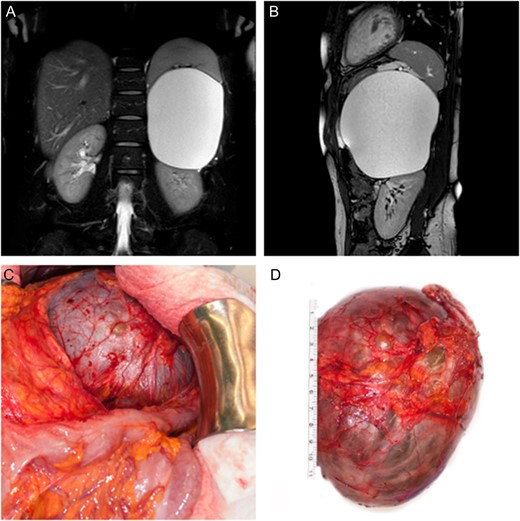

We performed an upper midline laparotomy. To ensure a good anatomical overview, mobilization of the left colonic flexure was necessary and the omental bursa was entered. The distal part of the pancreas showed close proximity to the cystic lesion and needed careful separation. After adhesiolysis between the splenic surface, the posterior gastric wall as well as the parietal peritoneum, the left adrenal gland with its associated vein, was found to be the origin of the cystic tumor. Hence total adrenalectomy was performed in order to remove the intact cystic lesion (Fig. 1C and D). Following a short period of postoperative nausea and vomiting, gradual return to a normal diet was possible. The patient was discharged on the sixth postoperative day.

The histological examination of the specimen revealed an adrenal lymphangioma located in a normal structured adrenal gland.

(A, B) Coronal and sagittal T2 weighted, fat suppressed MR image of the abdomen showing displacement of the spleen as well as the left kidney by the adrenal tumor. (C) Intra-operative finding showing close proximity of the cystic lesion to the left colonic flexure. (D) Surgically excised cystic tumor together with the left adrenal gland.